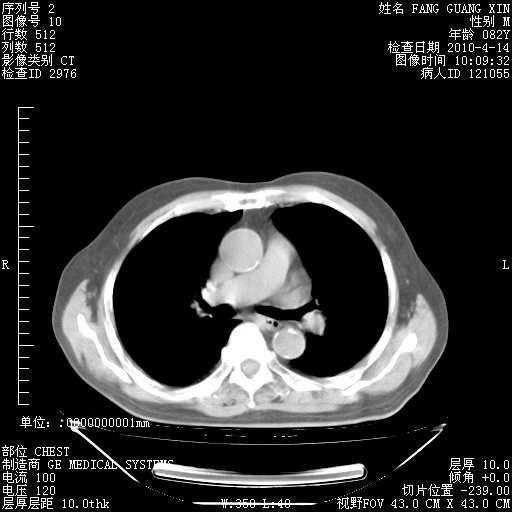

肺部CT平扫未见异常。